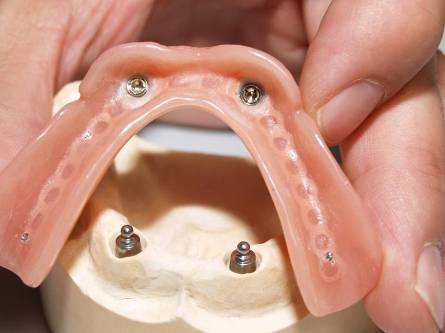

Bezzubá čelist je hlavní indikací pro ošetření pomocí implantátů. Zejména celkové zubní náhrady v dolní čelisti mají velice nízkou stabilitu a držení díky velkému úbytku kosti.

S pomocí zubních implantátů můžeme díky různým kotevním systémům (třmeny, kulové hlavy, Locatory) zajistit stabilitu a držení protézy nebo při použití většího počtu implantátů zhotovit pevné náhrady – můstky nalepené nebo našroubované na pevno na implantáty.

S těmito typy náhrad můžeme dosáhnout perfektní funkci, výbornou estetiku, fonetiku a současně zajistit u pacienta možnost dobré hygienickou péče a čištění, která je pro životnost implantátů velice důležitá.